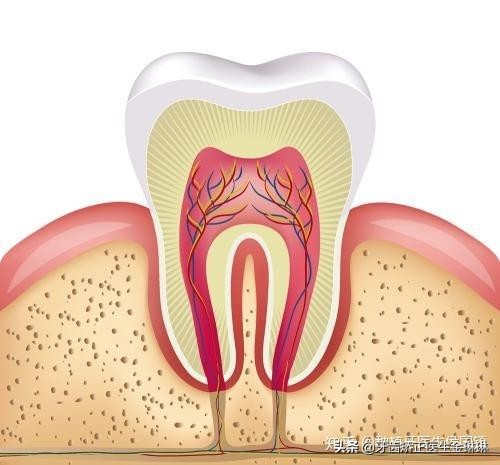

种植牙复诊通常主要是医生面诊检查种植牙周围组织的情况,并综合牙片以及术后反应等了解以及评估人工牙根植入到牙槽骨的结合情况。如果正常,则通常不需要做什么处理,如果有突发情况,医生需要及时判断处理。